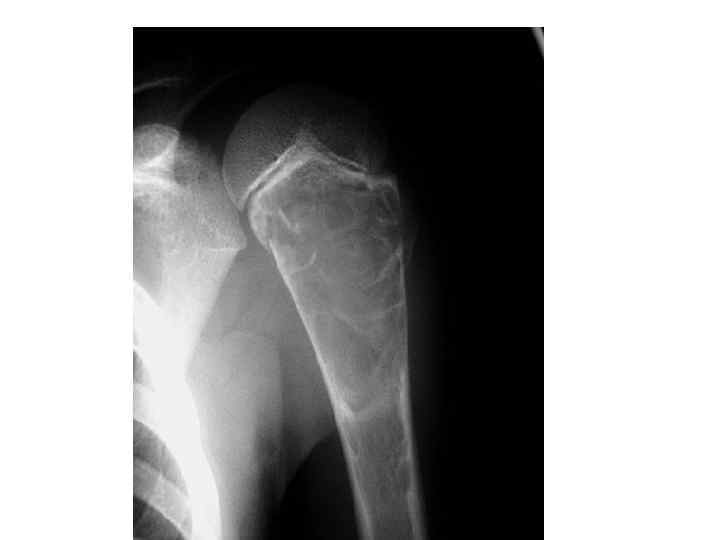

На рентгенограмме верхней половины левой плечевой кости в задней проекции определяется: в области проксимального метадиафиза плеча деформация плечевой кости в виде равномерного, умеренного ее вздутия за счет наличия здесь крупного, неправильно-овалной формы литического образования с ровными контурами размером 6, 5 на 4, 0 см, разделенного на несколько крупных ячеек. Кортикальный слой по периферии образования истончен в верхней его части разрушен как по медиальному, так и по латеральному контуру за счет поперечного патологического перелома. • Деструктивных и периостальных изменений не отмечается. Соседние участки кости не изменены. • Заключение: Учитывая возраст, локализацию, скиалогические особенности образования -картина изолированной костной кисты левой плечевой кости, осложненной патологическим переломом. •